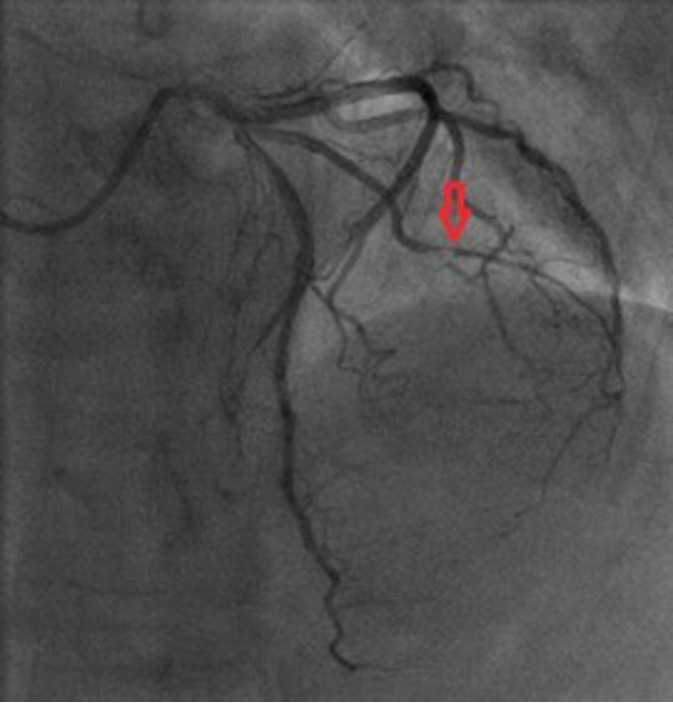

Case report: A 73-year-old patient, without comorbidities, was hospitalized for acute non ST-elevation myocardial infarction. Coronary angiography showed subocclusion of the first diagonal branch (culprit lesion) while the other epicardial coronary arteries were without stenosis. Multiple predilatations of the target vessel were performed, and as it was a vessel with a diameter of less than 2 mm, no stent was placed. The final angiogram showed normal flow and good morphological result. Half an hour after the procedure, cardiac tamponade and cardiorespiratory arrest developed. Emergency pericardiocentesis was performed and after the return of spontaneous circulation, emergency recoronarography was performed. It showed perforation of the diagonal branch with contrast extravasation. Coronary coil was applied proximal to the perforation site. Perforation repair and hemodynamic stabilization were achieved.